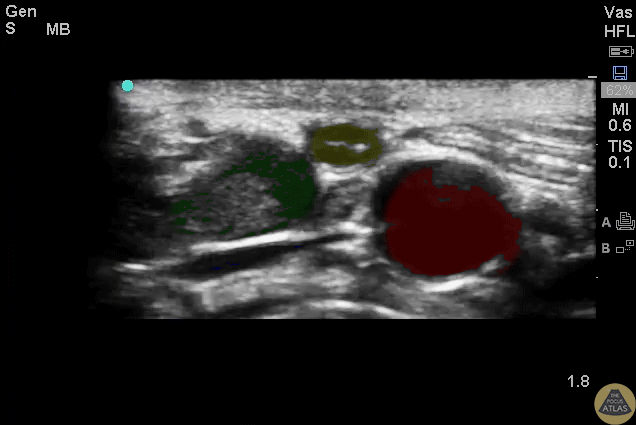

Normal appendix with landmarks highlighted. Green = Psoas Yellow = Appendix Red = Iliac Artery Blue = Iliac Vein Images provided by Sathya Subramaniam - Children’s Hospital of Philadelphia, edited by Matthew Riscinti - Kings County Emergency Medicine